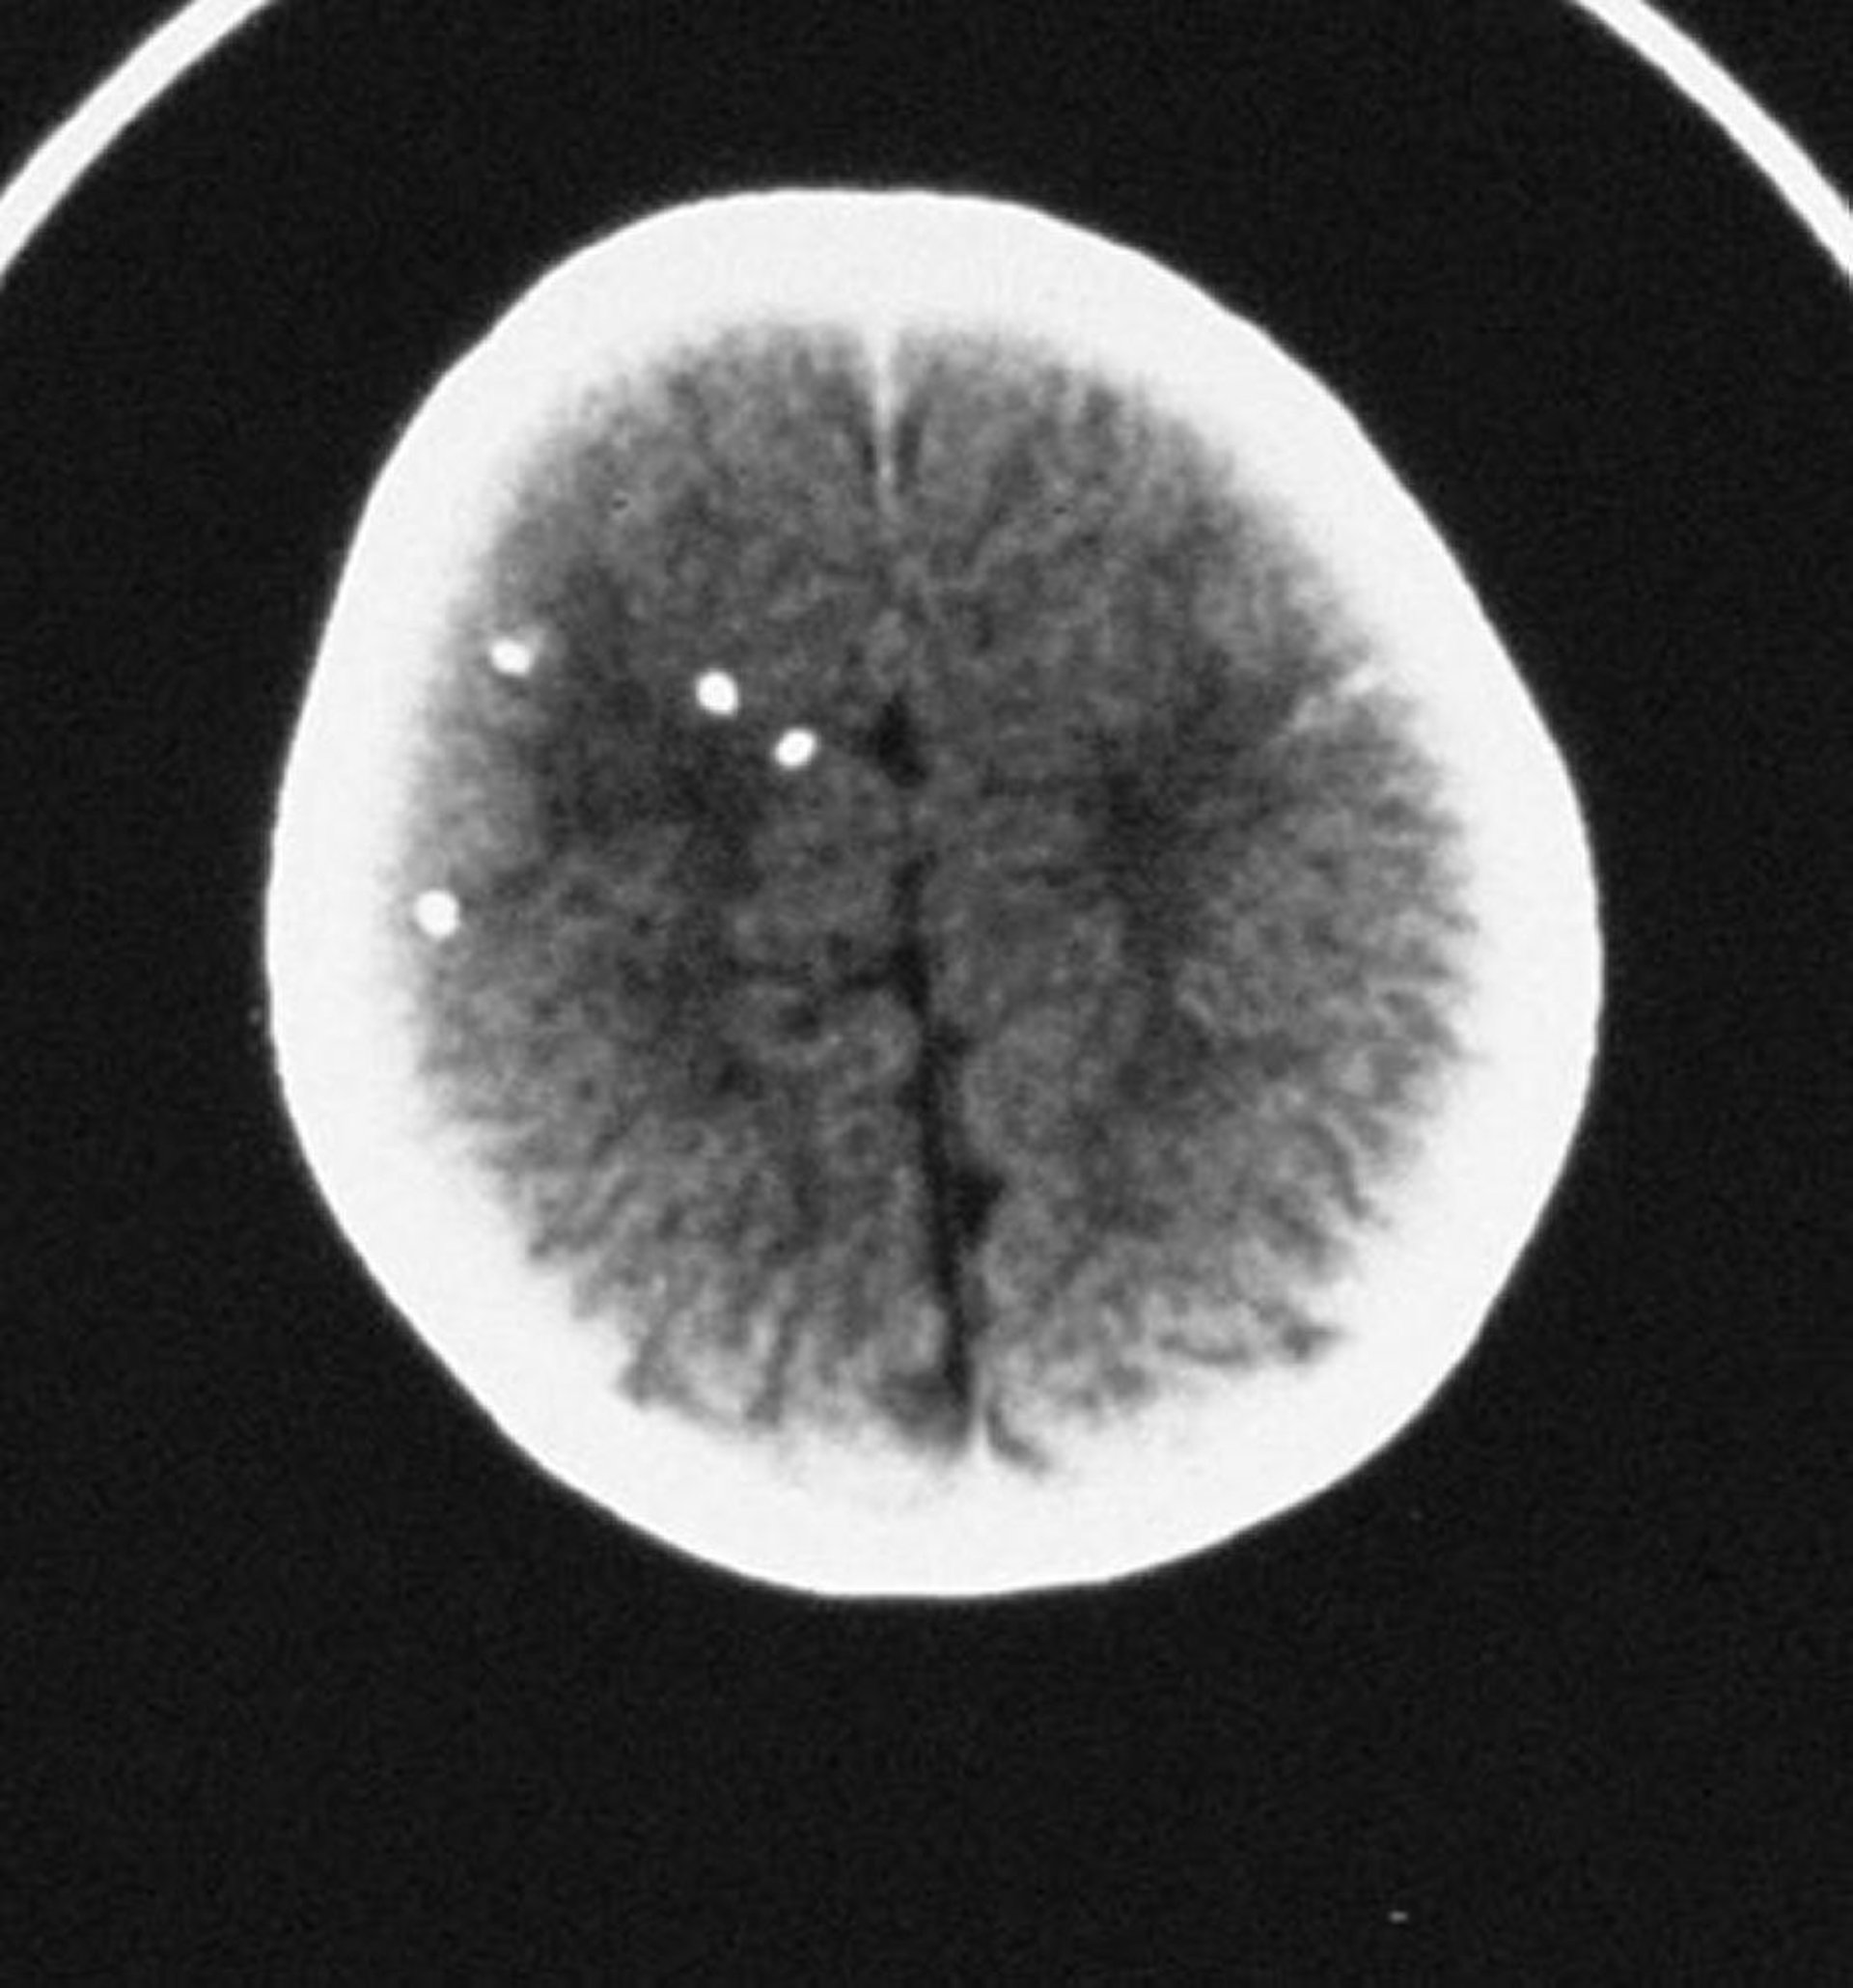

Il coinvolgimento neurologico, spesso predominante, comprende corioretinite, idrocefalo, calcificazioni endocraniche, microcefalia e convulsioni. La triade classica è costituita da corioretinite, idrocefalo e calcificazioni endocraniche. Le sequele neurologiche e oculistiche possono essere ritardate per anni o decenni.

Questa scansione TC mostra calcificazioni intracraniche diffuse.

By permission of the publisher. From Demmler G: Congenital and perinatal infections. In Atlas of Infectious Diseases: Pediatric Infectious Diseases. Edited by CM Wilfert. Philadelphia, Current Medicine, 1998.